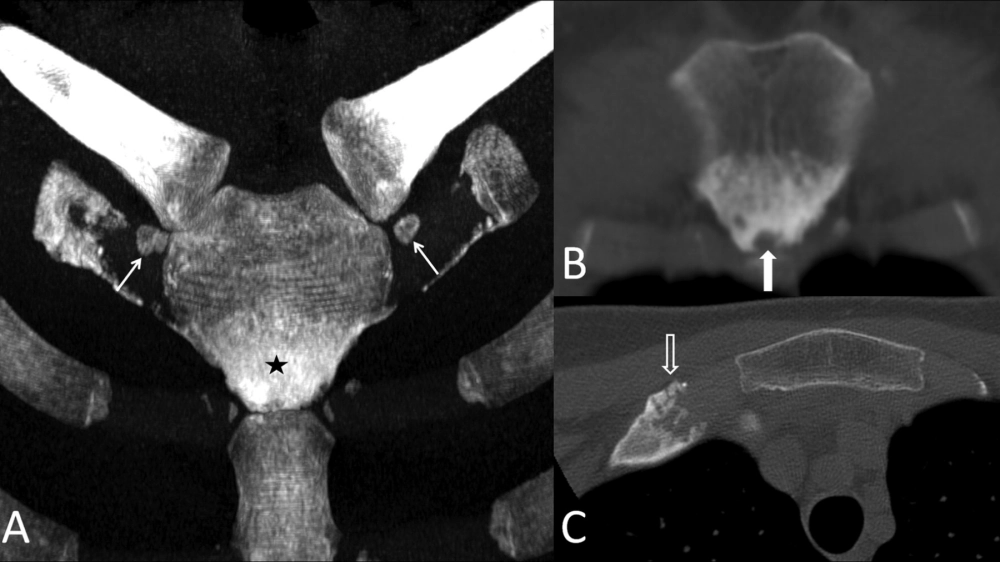

• Triệu chứng bệnh Paget xương phổ biến nhất là đau xương. Xương có thể bị biến dạng, cong vẹo, dễ gãy và gây chèn ép các dây thần kinh.

• Các triệu chứng khác có thể bao gồm da ấm hơn ở vùng xương bị ảnh hưởng, đau đầu, giảm thính lực nếu bệnh Paget ảnh hưởng đến xương sọ.

X-quang cho thấy sự biến dạng của bệnh Paget xương